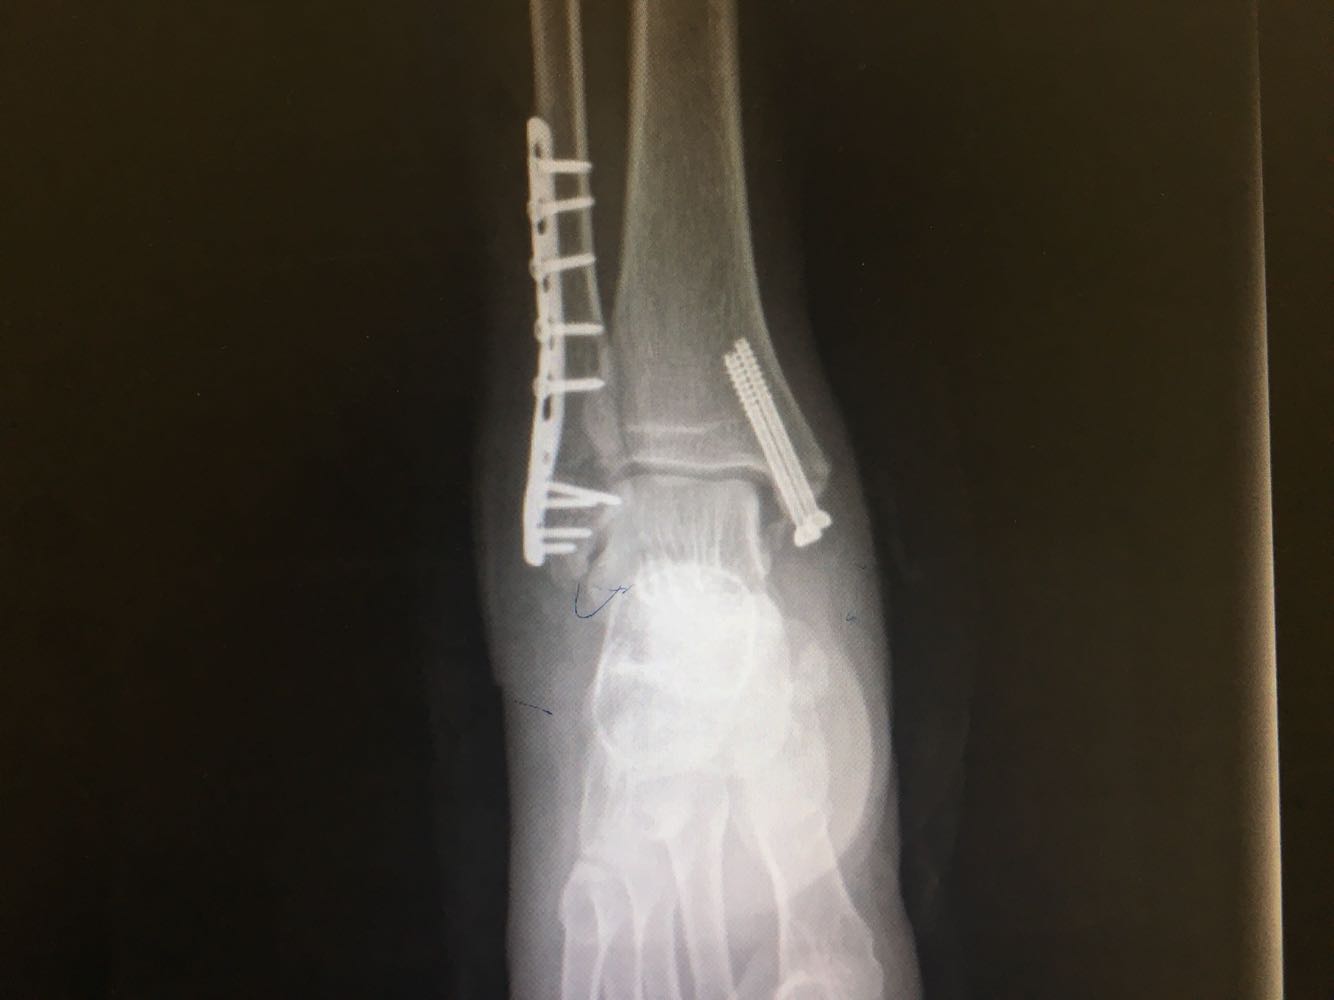

患者,男,54岁。 主诉:外伤致右踝疼痛伴活动受限2天 现病史:患者于2天前不慎扭伤致右踝疼痛,伴活动受限,否认头晕头痛、恶心呕吐等不适,就近医院就诊,查X片示:右踝骨折,予石膏外固定,现为进一步诊治收治入院,发病以来,神清,精神可,胃纳夜眠可,二便无殊,体重无明显变化。

查体:右踝压痛,活动受限,无淤斑淤点,未见皮肤破损,足趾感觉及运动良好。 辅检:右踝部CT

诊断:右侧踝部闭合性骨折 治疗:完善术前检查后行手术内固定